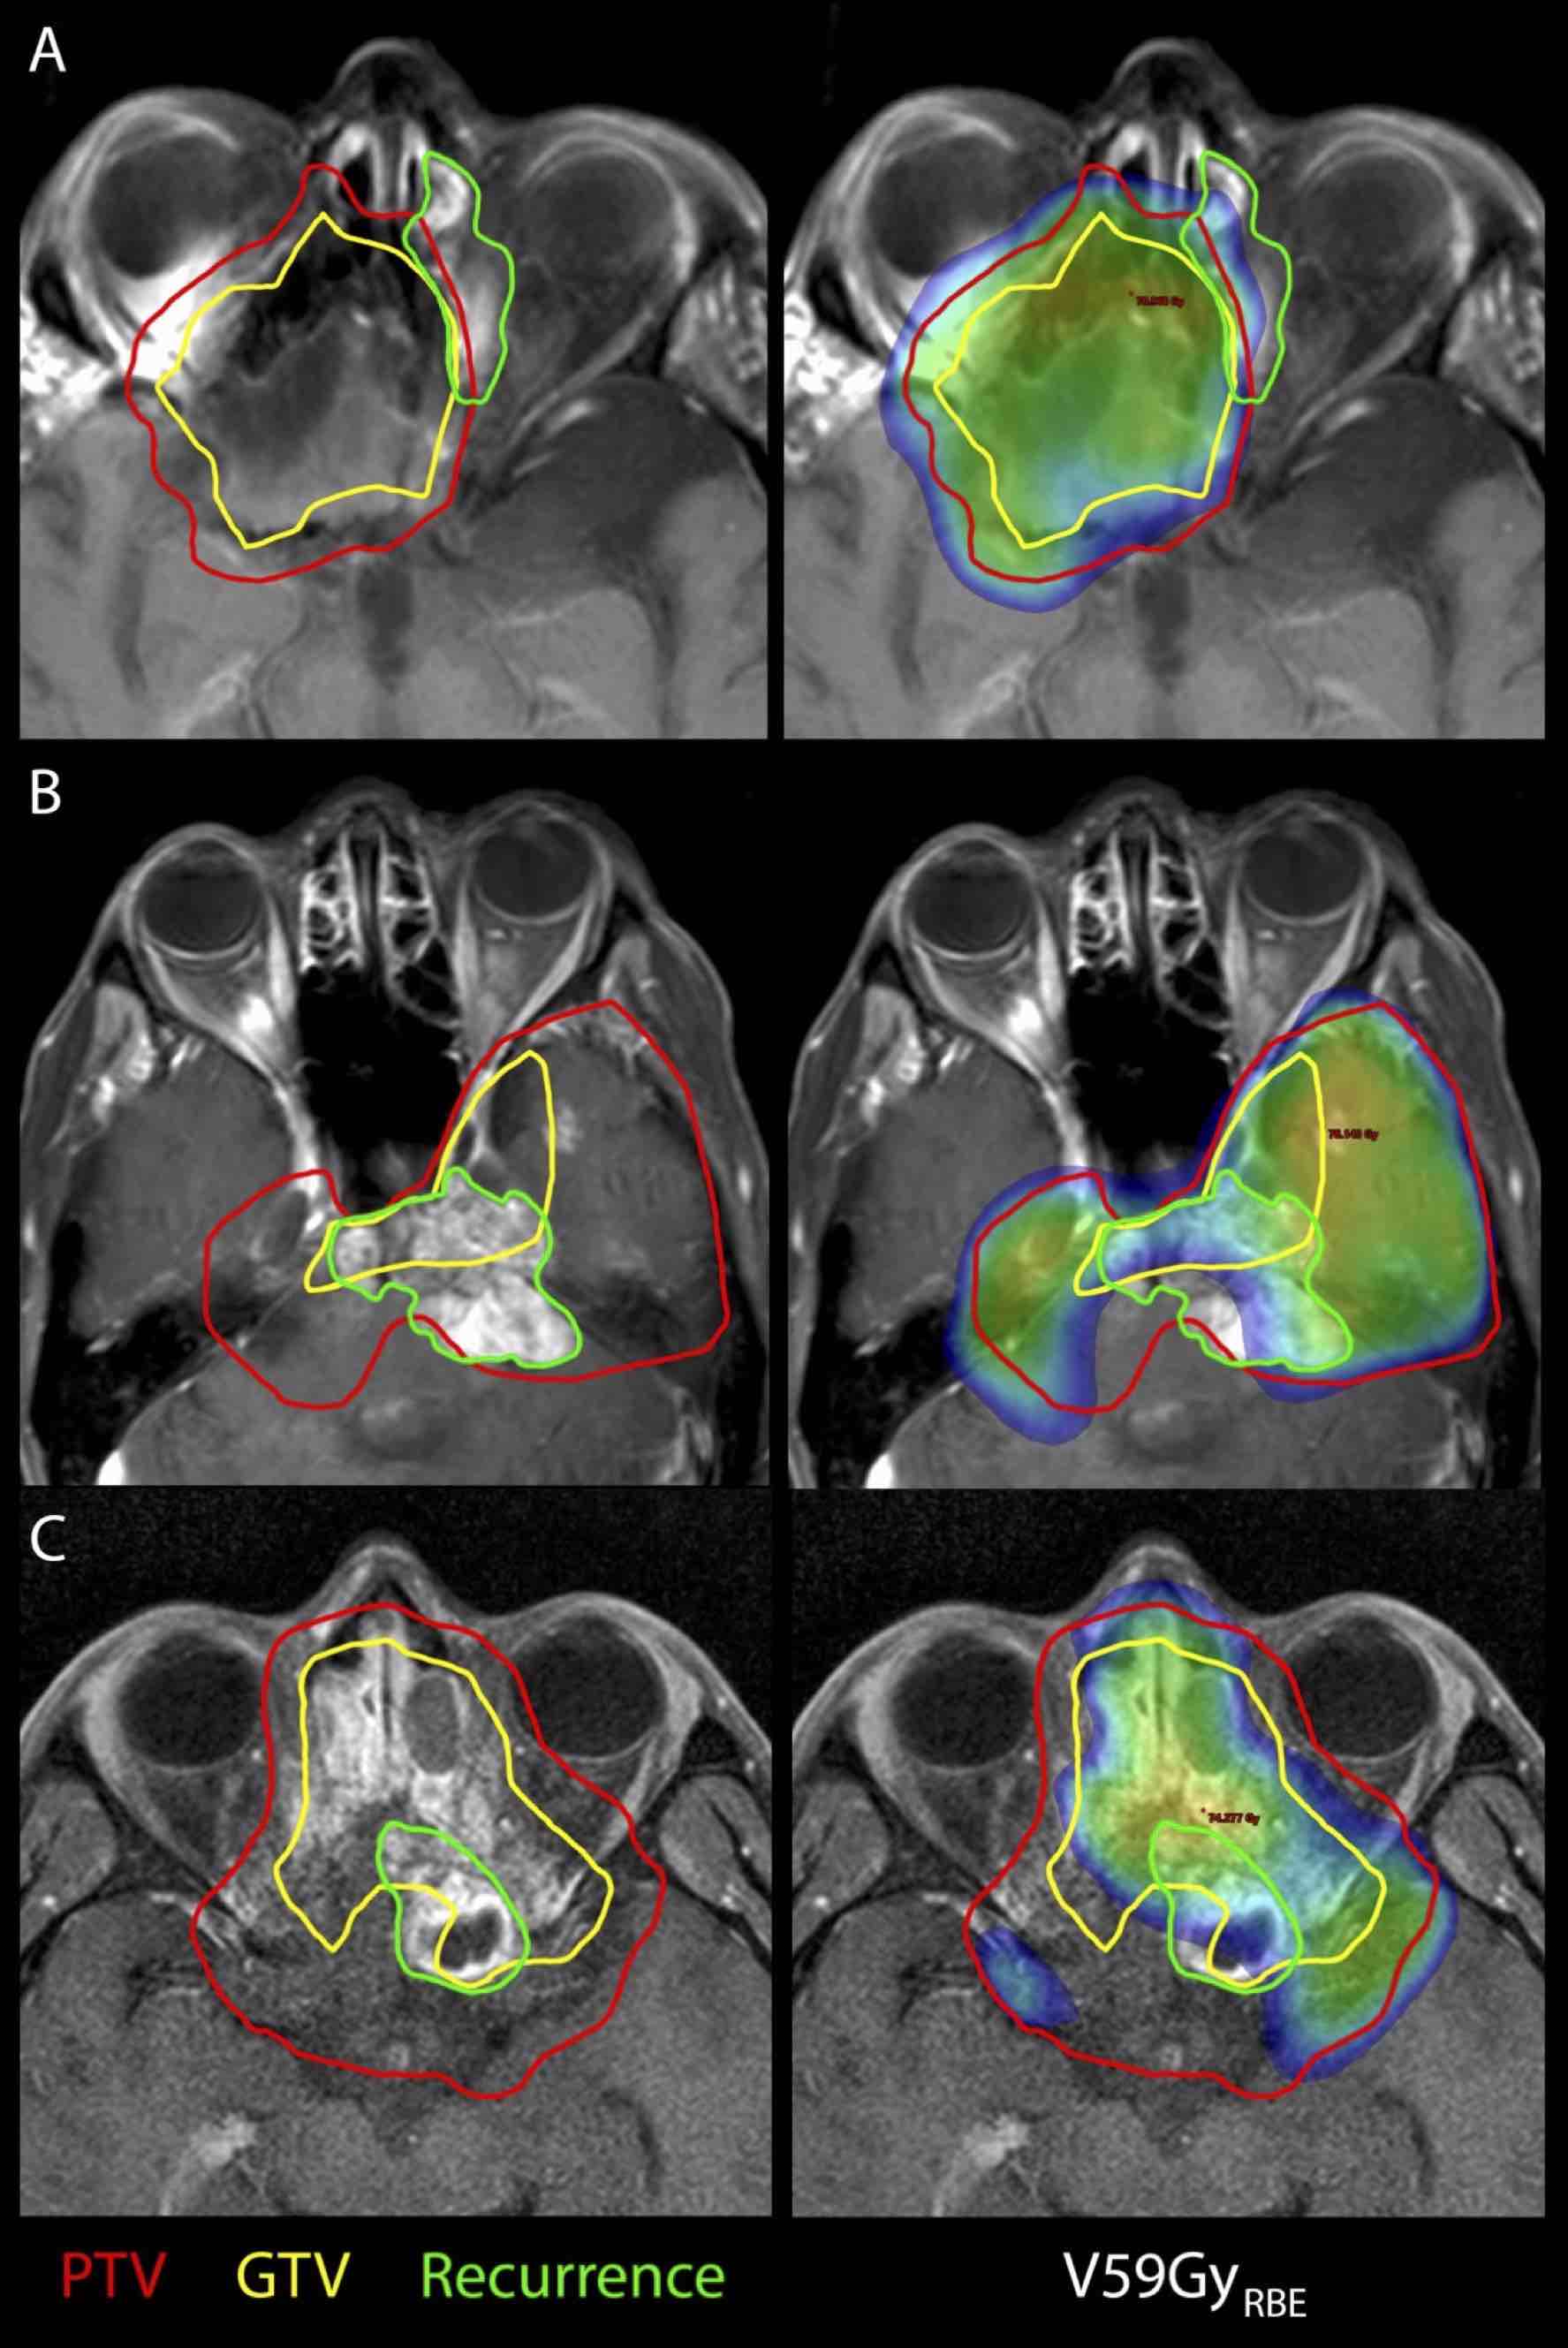

Dosimetric analysis of local failures in skull-base chordoma and chondrosarcoma following pencil beam scanning proton therapy

Despite combined modality treatment involving surgery and radiotherapy, a relevant proportion of skull-base chordoma and chondrosarcoma patients develop a local recurrence (LR). This study aims to analyze patterns of recurrence and correlate LR with a detailed dosimetric analysis.

222 patients were treated with proton radiotherapy for chordoma (n = 151) and chondrosarcoma (n = 71) at the PSI between 1998 and 2012. All patients underwent surgery, followed by pencil-beam scanning proton therapy to a mean dose of 72.5 ± 2.2GyRBE. A retrospective patterns of recurrence analysis was performed: LR were contoured on follow-up MRI, registered with planning-imaging and the overlap with initial target structures (GTV, PTVhigh-dose, PTVlow-dose) was calculated. DVH parameters of planning structures and recurrences were calculated and correlated with LR using univariate and multivariate cox regression.

This study identified DVH parameters, which are associated with the risk of local recurrence after proton therapy using pencil-beam scanning for patients with skull-base chordoma and chondrosarcoma.